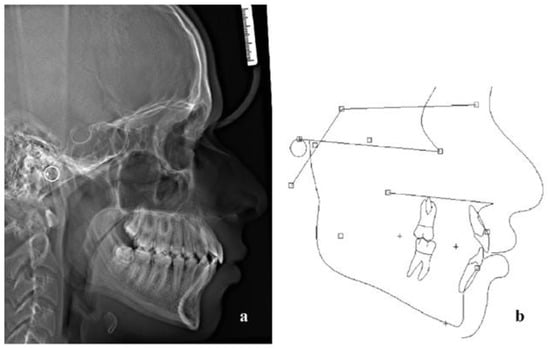

| Measurement | Mean ± SD | Pretreatment | Posttreatment |

|---|---|---|---|

| 1. SNA (°) | 81 ± 3 | 88.1 | 89 |

| 2. SNB (°) | 78 ± 3 | 83 | 84.2 |

| 3. ANB (°) | 3 ± 2 | 5.1 | 4.9 |

| 4. Wits (mm) | 1 ± 2.9 | 0.1 | 0.8 |

| 5. GoGN/SN (°) | 32.5 ± 5.2 | 27.1 | 25.8 |

| 6. U1/PP (°) | 109 ± 6 | 125.9 | 117.1 |

| 7. L1/MP (°) | 93 ± 6 | 110.8 | 94.5 |

| 8. Interincisal angle (°) | 135 ± 10 | 104.6 | 130.2 |

| 9. Labionasal angle (°) | 95.96 ± 2.57 | 106.6 | 99 |